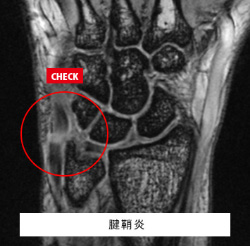

手関節MRI

腱鞘炎 舟状骨骨折

主な疾患:TFCC損傷、ガングリオン、尺骨突き上げ症候群、ドケルバン病、手根骨骨折など

手関節の痛みや可動域制限がある方におすすめします。

多くの骨や軟骨、筋肉、靭帯から構成される関節であり、20~30分程度の長い時間をかけて総合病院と同等の詳細な検査を施行いたします。

検査費用(片側):¥27,500(税込)